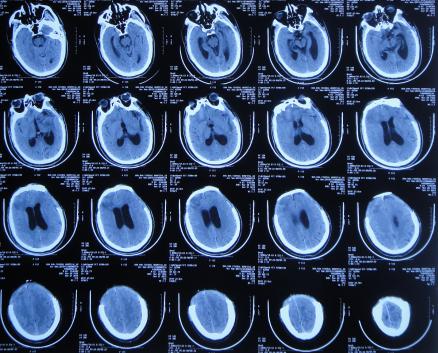

继续治疗1周时间内,曾3次复查头颅CT( 图-5、图-6、图-7 )均示脑膨出逐渐加重的趋势,仍有积血;期间给予腰大池引流。

图-5: 2019年10月26日头颅CT

图-6: 2019年10月29日头颅CT

图-7: 2019年10月31日头颅CT

开颅术后14天即2019年11月3日,虽仍有些积血,但脑膨出有好转( 图-8 ),意识也变清。

图-8: 2019年11月3日头颅CT

开颅术后18天即2019年11月7日,脑膨出进一步好转( 图-9 )。

图-9: 2019年11月7日头颅CT

开颅术后26天即2019年11月15日,查头颅CT示积血基本消失,脑膨出变正常( 图-10 )。

图-10: 2019年11月15日头颅CT

开颅术后30天即2019年11月19日,出现走路不稳,查颈椎核磁( 图-11 )后认为无明显异常。

图-11: 2019年11月19日腰椎核磁

开颅术后33天即2019年11月21日,查头颅CT( 图-12 )后认为无明显异常随后出院。

图-12: 2019年11月21日头颅CT